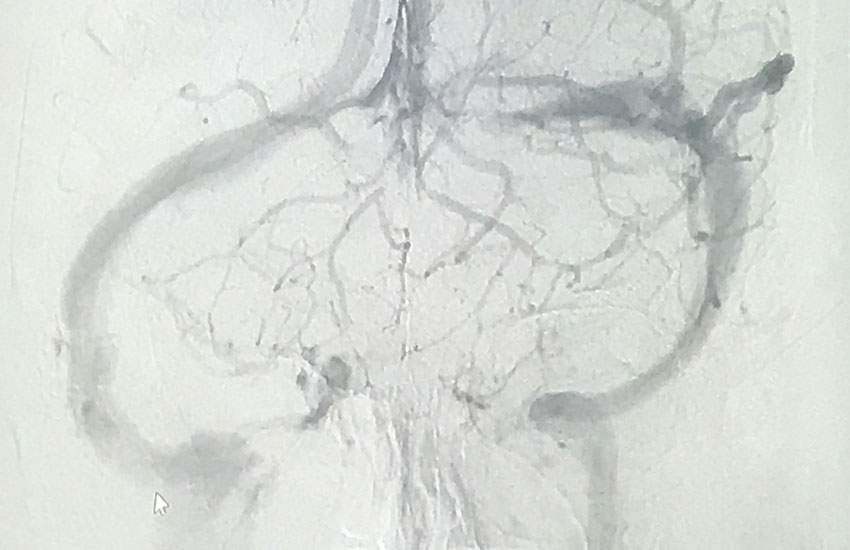

Η διάγνωση της καρωτιδικής νόσου γίνεται μέσω έγχρωμης υπερηχογραφίας (triplex) των καρωτίδων. Ακολουθεί CTA ( αξονική αγγειογραφία ) αγγείων τραχήλου – εγκεφάλου για προσδιορισμό της έκτασης της αθηρωματικής πλάκας και ανατομίας της περιοχής.